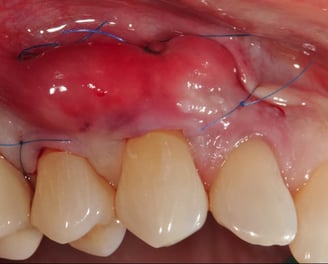

Tratamiento de recesión gingival

Se corrige la retracción de las encías que deja expuestas las raíces dentales. Esto puede implicar injertos de encía o técnicas quirúrgicas para restaurar la posición original de las encías.

Se realiza para cubrir áreas de recesión gingival o mejorar la calidad del tejido periodontal. Consiste en tomar un injerto de encía de otra parte de la boca y colocarlo en el área afectada.

Injerto de Encía